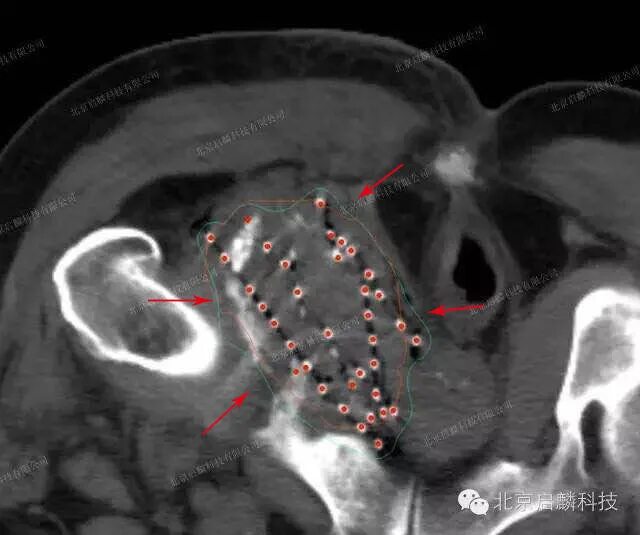

Метастазы в лимфоузлах форум